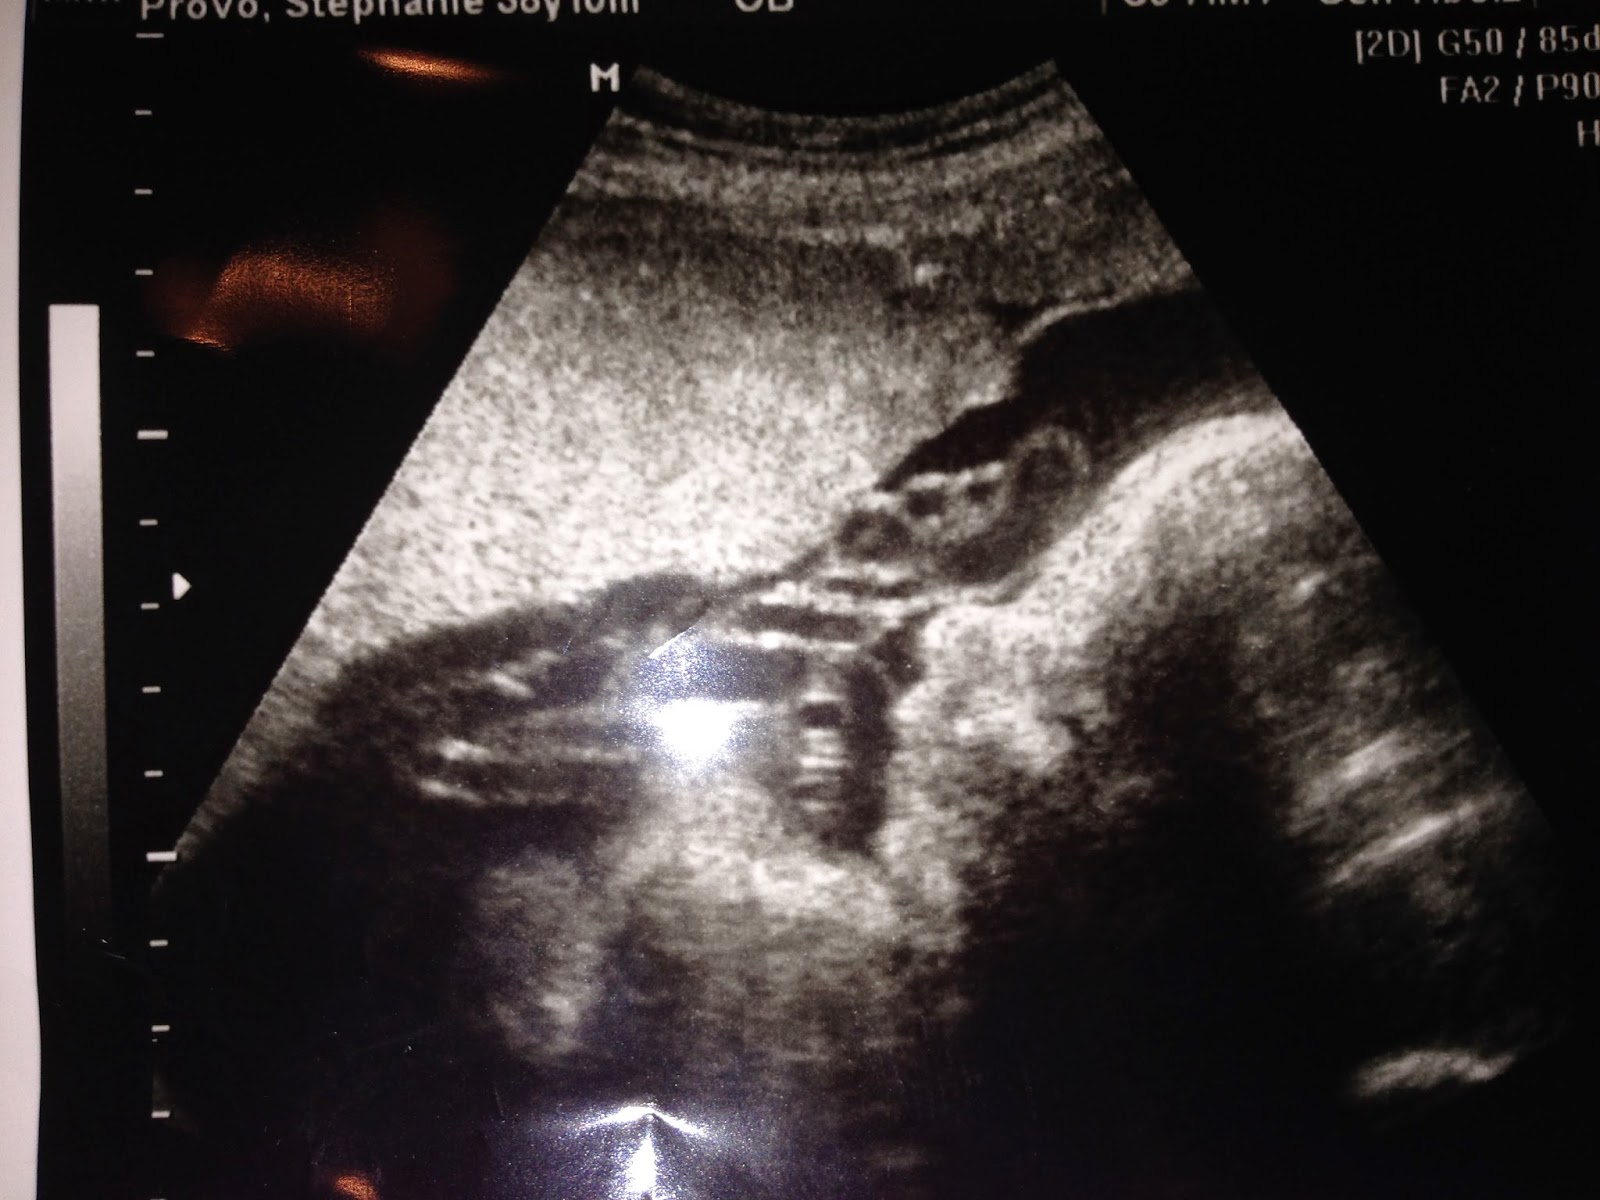

Doesn't Stephanie look great? Her belly measures that of a full term pregnancy! The babies are amazing! They have grown like champs! Baby A is huge! She is already 5 1/2 pounds (bigger than K at 35 1/2 weeks)! Baby B is almost there as well! She is 4 1/2 pounds! They both are doing great! The doc doesn't think they will make it past 35 weeks! I am praying they stay in until 36 +. The doc will induce at 37 weeks if they haven't made their appearance!

They checked Stephanie while we were there! She is 2 cm dialated ( you can stay like this for awhile) 70% effaced (which is great! 100% means that is as thin as the cervix gets---paper thin) and at -2 station! She her body is getting ready!